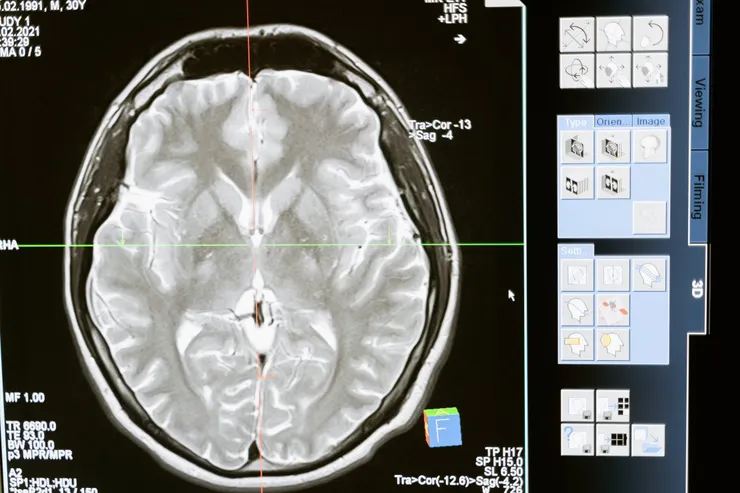

我最近開始與之合作的另一個車禍客戶,他的頭頂縫了很多針。他的創傷導致內出血、疼痛、混亂、激動和抑鬱。當醫務人員告訴他他有腦外傷時,他否認了這一點。他的母親問他是否願意接受靈氣。由於他還有其他一些傷病,所以他同意接受靈氣。在康復後的六週內,醫生在進行腦部掃描和測試後指出,他的大腦癒合得很好。我們正在繼續治療的流程。

The other car accident client that I recently began working with, had many stitches over the top of his head. His trauma caused internal bleeding, pain, confusion, agitation, and depression. When the medical staff told him he had brain trauma he is in denial about it. His mother asked him if he would be open to receiving Reiki. He had a number of other injuries as well so he agreed to receive the Reiki. Within six weeks of being in rehab, the doctors noted, after doing brain scans and testing, that his brain was healing quite well. We are continuing sessions.